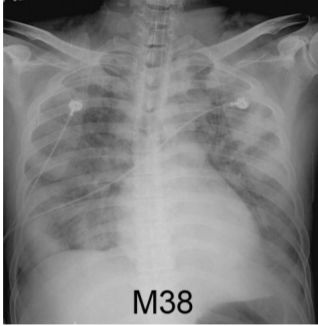

6. 男性38歲,有吸煙史,因發燒、咳、喘來急診,胸部X光如圖1,隔天喘加劇、胸部X光如圖2,其最可能診斷為何? (A) 流感肺炎 (B) 葡萄球菌肺炎 (C) 綠膿桿菌肺炎 (D) 克雷白 ( Klebsiella ) 菌肺炎 (E) 退伍軍人症肺炎